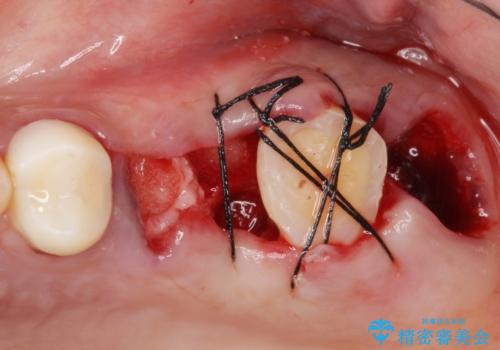

奥歯3本(左上567)はう蝕が深く保存不可能な状態であったため、やむなく抜歯しました。

使っていない親知らず(左上8)を左上7抜歯窩に移植し、支台歯としてブリッジによる補綴治療を行いました。